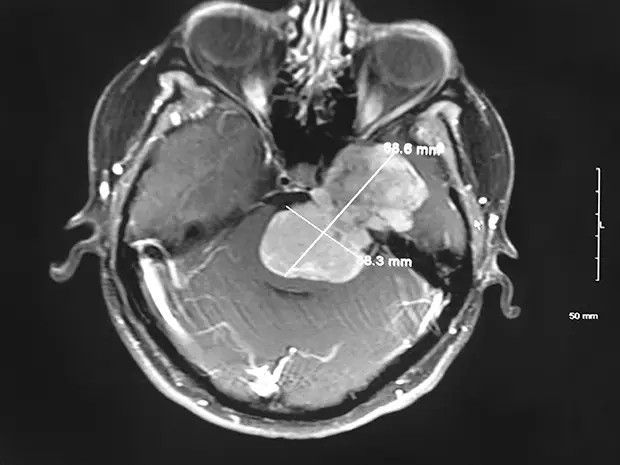

Brain Tumors When Timing Is Critical

Central Illinois Neuro Health Sciences